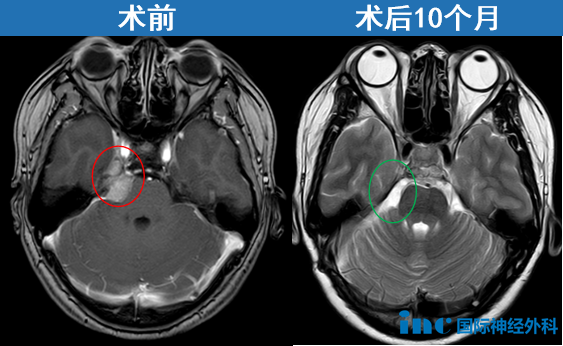

“我不說(shuō),沒(méi)人知道我腦子開(kāi)了刀”,和許多經(jīng)由INC巴教授國(guó)內(nèi)成功手術(shù)患者類(lèi)似的是,開(kāi)顱術(shù)后10個(gè)月,狀態(tài)好到很難想象她開(kāi)過(guò)顱。巴教授也為她高興:"腫瘤完全切除,無(wú)任何并發(fā)癥。在臨床恢復(fù)方面,我非常高興看到患者目前神經(jīng)功能狀態(tài)良好,尤其面神經(jīng)及第六腦神經(jīng)功能完全保留。衷心祝愿她一切順利。建議于2026年夏季進(jìn)行下一次 MRI 復(fù)查,屆時(shí)我可以再次評(píng)估其影像學(xué)表現(xiàn)。"

影像